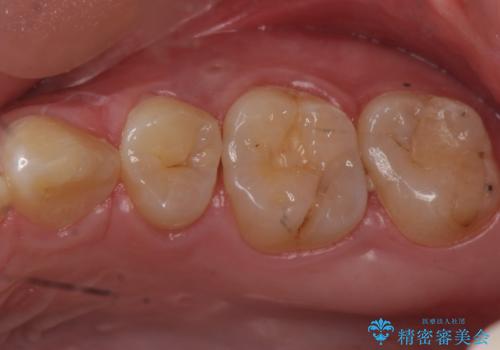

歯と歯の間によくものが詰まる。。セラミック治療

銀の詰め物を白い物にしたい